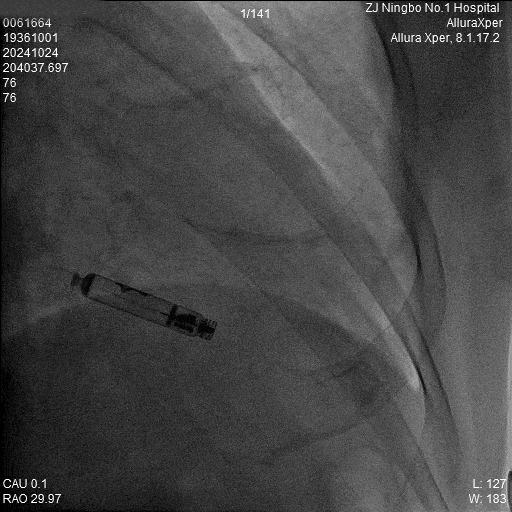

4.旋入起搏器:回撤保护套筒至下腔,释放调弯,调整张力开始旋入旋入0.5圈及1.0圈分别测试参数,等待扭矩传递。

6.释放:释放Aveir VR后,最终影像图。

a)AP